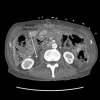

Cast syndrome, commonly known as superior mesenteric artery (SMA) syndrome is a rare cause of small bowel obstruction caused by compression of third part of duodenum from narrowing of the angle between superior mesenteric artery and abdominal aorta resulting in symptoms of duodenal outflow obstruction. A 46-year-old male presented with acute worsening of chronic abdominal pain, nausea and vomiting aggravated with eating. Computed tomography of abdomen and pelvis revealed the dilatation of gastric and proximal duodenum due to compression of third part of duodenum between superior mesenteric artery and aorta. Conservative management with total parental nutrition failed and patient underwent gastrojejunostomy with relief of his symptoms. Cast syndrome is a rare condition but should be kept in mind in patients with abdominal pain, vomiting, early satiety and weight loss. CT abdomen usually reveals the diagnosis but upper GI endoscopy helps to rule out other causes of duodenal obstruction and gastric dilatation.